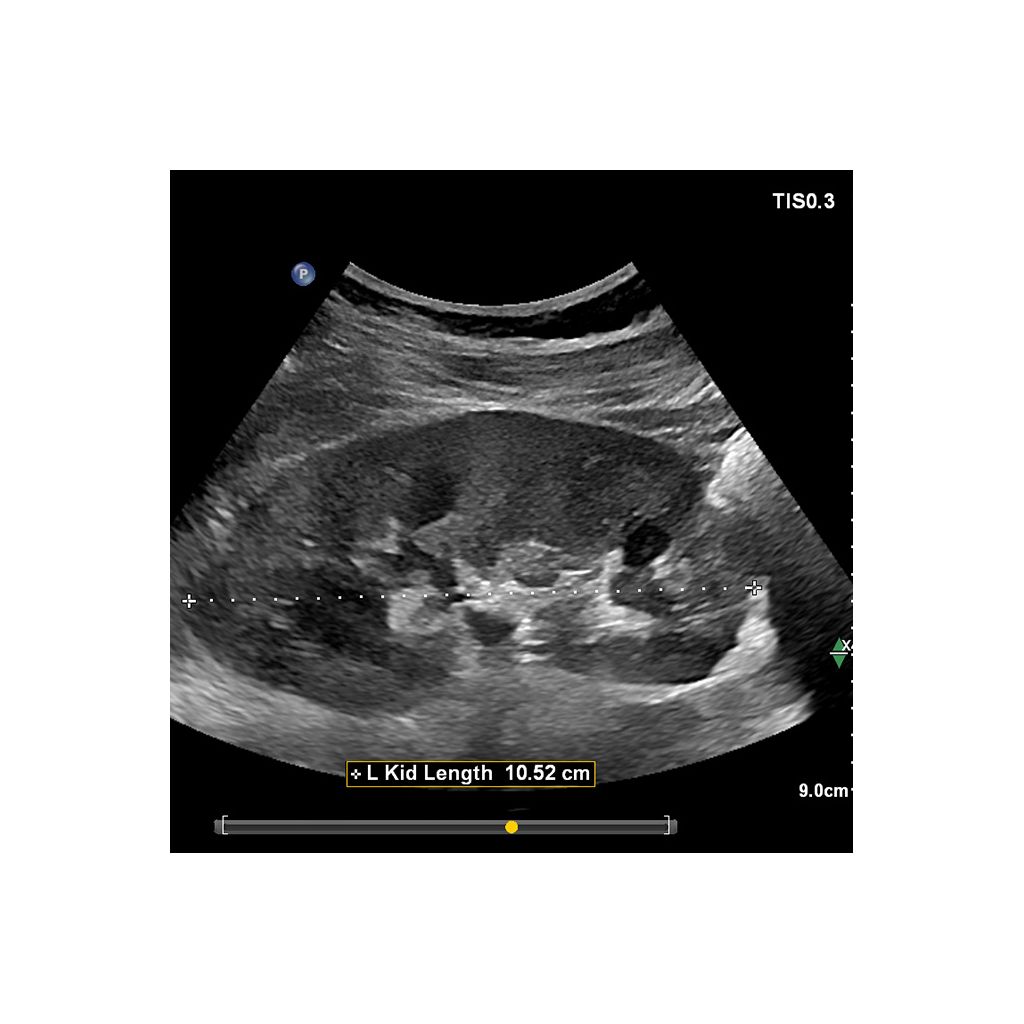

AI-driven Auto Measure Abdomen - Philips